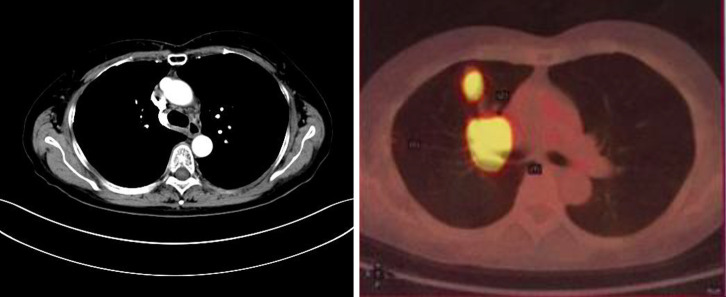

Case description: We report the case of a 65-year-old female patient with advanced lung adenocarcinoma (LUAD) who developed bone and adrenal gland metastases following treatment with gefitinib. Next-generation sequencing (NGS) of a biopsy specimen revealed the co-occurrence of MET amplification and EGFR exon 19 deletion mutation. The combined treatment of savolitinib and gefitinib effectively controlled the disease, resulting in a favorable long-term clinical outcome. With continued follow-up through April 2025, the patient has maintained progression-free survival (PFS) over 8 years. However, monitoring revealed the patient had grade 4 peripheral edema, and negative circulating tumor DNA (ctDNA), which necessitated a savolitinib dose reduction. Subsequent minimal residual disease (MRD) assessments and radiological scans revealed a remarkable therapeutic response with sustained efficacy.